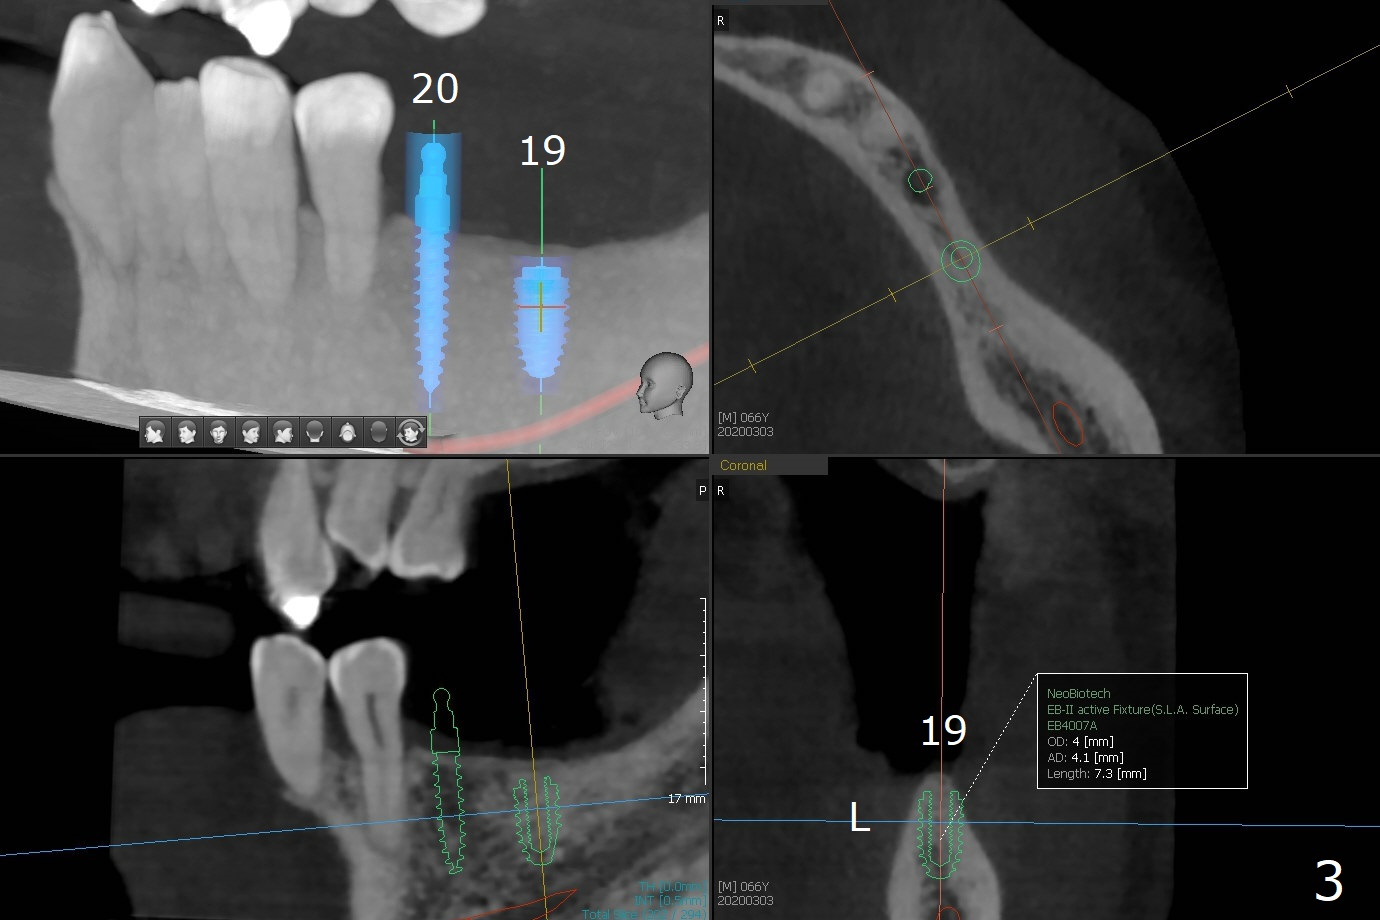

When implants at #4, 13 and 14 are placed, the patient wonders how many more implants are needed. From 0 (considering a lower RPD) to 5 (#3, 19, 20, 25 and 30). The tooth #3 seems to have periodontal-endodontic disease (Fig.1,2). Since the ridge is narrow at #19 and 20 (Fig.3), ridge split at #19 and a 1-piece implant at #20 are planned (Fig.4,5-9). The implant at #19 will be placed in an ideal prosthetic position (Fig.5). The ridge transverse bony cut will be made free hand in the middle (Fig.6,6'), followed by 2 vertical cuts and 1 apical transverse one in the 1st stage of procedure. In order to rotate the buccal block easier (Fig.6 pink curved arrow), the apical transverse cut will be wedge in shape (Fig.6 (red), 6' (double lines), 7 (black)). In the 2nd stage, the ridge top split will be extended by using a chisel (Fig.7 longer red line) and the buccal block will be pushed buccally (Fig.8). A guide will be seated to finish osteotomy (Fig.9 white) and implant placement.

While the ridge at #30 is normal for a normal sized implant (Fig.10,11), the one at #25 is not (Fig.12, a 2 mm 1-piece implant).